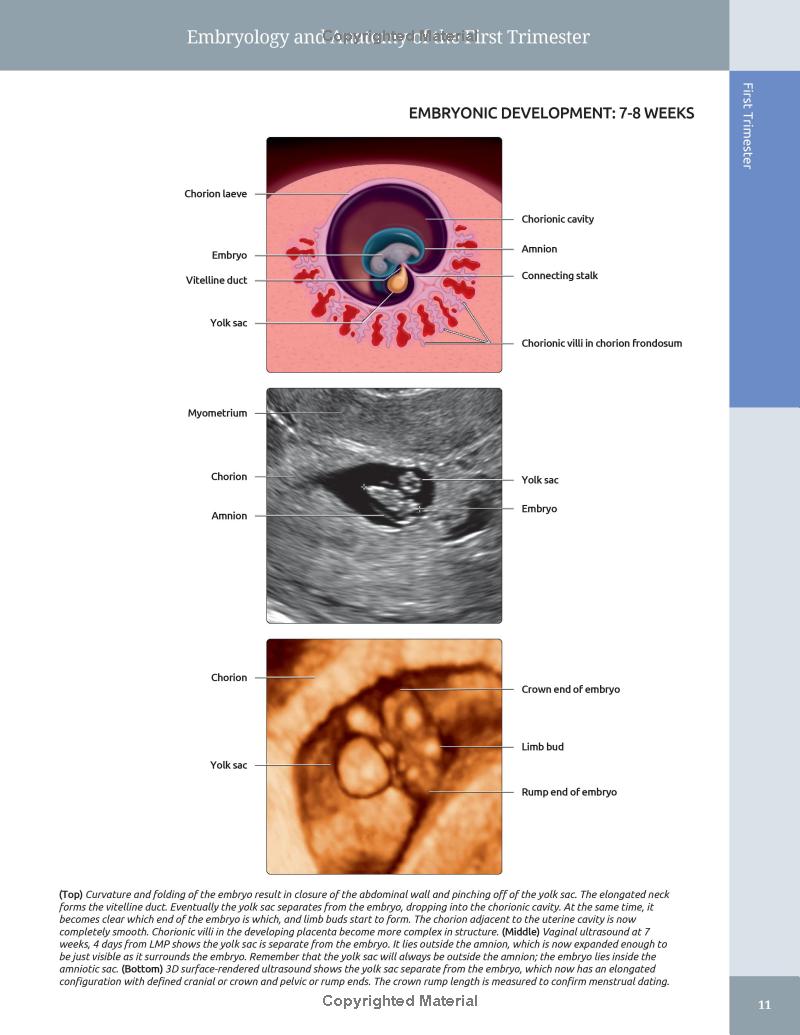

- Features expanded embryology chapters delineating normal developmental anatomy

- Richly colored graphics and fully annotated images highlight the most important diagnostic possibilities